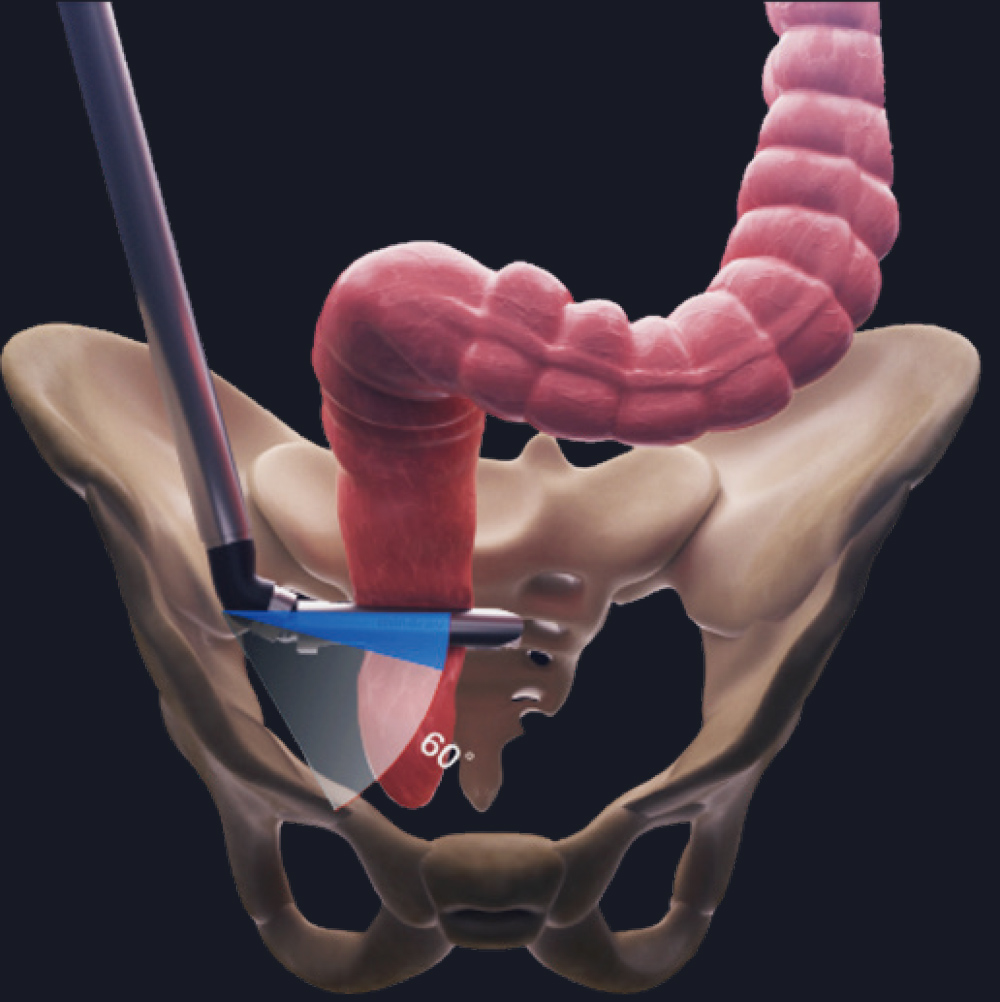

60┬░ Articulating Angle,

Providing Exceptional Flexibility

In narrow anatomical cavities such as the lower anterior rectum, left upper lung, and gastroesophageal junction, 60┬░arti culation allows for precise placement and dissection.